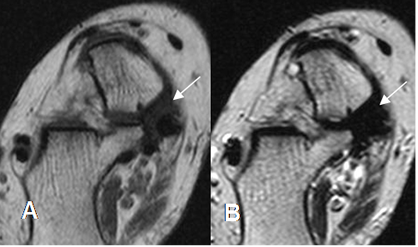

Fig 118 A. Sindrome del tarso.

A: RM axial en T1 y B: RM axial en T2. Tejido blando fibroso en la parte medial del pie, que rodea el tendón del tibial posterior y ocasiona sindrome del tarso.